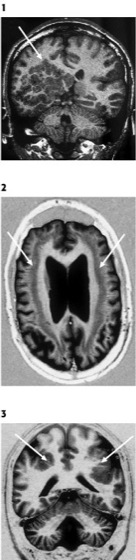

Heterotopien sind Ansammlungen normaler Neurone in abnormer Lokalisation, in der Folge von Störungen der radialen Migration, die durch sehr unterschiedliche Faktoren bedingt sein können. Man unterscheidet subependymale (periventrikuläre) noduläre Heterotopien von fokalen (nodulären) subcorticalen ( siehe Abb. 1 ), bandförmig diffusen (laminären; siehe Abb. 2 ) und subpialen (leptomeningialen glioneuronalen) Heterotopien. Diese Fehlbildungen können isoliert oder in Kombination mit anderen Gehirnanomalien auftreten. Bandheterotopien kommen als X-chromosomal gebundene Fehlbildungen vor. In betroffenen Familien zeigen vorwiegend Frauen die Heterotopien, während bei Knaben Lissencephalien auftreten. Auch bilaterale periventrikuläre noduläre Heterotopien treten als X-chromosomale Fehlbildung auf. Heterotopien sind besonders häufig mit Epilepsien assoziiert, wobei epileptische Aktivität in den heterotopen Neuronen selbst nachgewiesen werden konnte.

Als Polymikrogyrien wird das Vorliegen von abnormen, in ihrer Anzahl vermehrten und in ihrer Größe verminderten, unvollständig bzw. nur durch flache Sulci voneinander getrennten Windungen bezeichnet ( siehe Abb. 3 ). Die Gehirnoberfläche weist im Bereich der Polymikrogyrien ein blumenkohlartiges Aussehen auf. Der Cortex ist abnorm verbreitert, jedoch nicht so dick wie bei Pachygyrien. Polymikrogyrien können eng umschrieben oder weit ausgedehnt vorkommen. Gehäuft findet man sie einseitig oder beidseitig in der Umgebung der Sylvius-Furche. Bei Polymikrogyrien konnten laminäre Nekrosezonen mit Schwerpunkt in der 5. Rindenschicht bei vorhandener Schichtengliederung des Cortex nachgewiesen werden. Eine Verursachung durch verminderte Durchblutung (Ischämie) nach der 20. Gestationswoche, d.h. eine postmigratorische Störung, wird für die meisten Fälle als ursächlich angenommen. Bei Polymikrogyrien mit fehlender Rindenschichtung ist eine frühere Schädigung zu postulieren. Durch perinatale Durchblutungsstörungen entstandene Schädigungen mit Verkleinerung der Windungen werden Ulegyrien genannt; sie sind von Polymikrogyrien zu unterscheiden und nicht den Fehlbildungen zuzuordnen (da perinatal). Bei der Schizencephalie wird der gleiche Entstehungsmechanismus wie bei den Polymikrogyrien angenommen. Es besteht eine mehr oder weniger breite liquorgefüllte Lücke, die vom Ventrikel bis zur Gehirnoberfläche reicht und bis in die Tiefe von einem Band grauer Substanz gesäumt ist. Übergänge von reinen Polymikrogyrien bis zur vollständigen Schizencephalie (Polymikrogyrien mit "infolding", "open-" und "closed-lip-"Schizencephalie) werden angenommen. In etwa einem Drittel der Fälle kommen Schizencephalien beidseitig vor. Die häufig auf ausgedehnte Infarkte oder Blutungen zurückgehenden Porencephalien sind später entstehende (encephaloklastische) Läsionen und weisen im Gegensatz zu Schizencephalien keine randständige graue Substanz auf.

1 kernspintomographische Darstellung in coronaren T1-gewichteten Sequenzen, die ausgeprägte regionale subcorticale noduläre Heterotopien (Pfeil) zeigt.

2 kernspintomographische Darstellung in transversalen Inversion-Recovery-Sequenzen, die beidseitig subcorticale bandförmige Heterotopien (Pfeile) zeigt.

3 kernspintomographische Darstellung in coronaren Inversion-Recovery-Sequenzen, die beidseitig parietale Strukturauffälligkeiten der Rinde zeigt (Pfeile), welche am ehesten Polymikrogyrien entsprechen dürften.